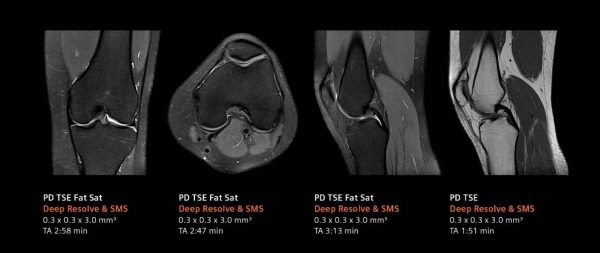

デジタル化により高画質と撮像時間の短縮を実現するべく、画像再構成にAI技術を用いて開発されたのがDeep Resolve(ディープ・レゾルブ)だ。

Deep Resolveは、ディープラーニング(深層学習)とターゲットデノイジング(ノイズの標的除去)により画像のノイズ除去や撮像した画像を高分解能化することで、高品質な画像の取得と撮影時間の短縮*1を可能にする。検査精度やワークフローの向上のほか、被検者の快適性や質の高い医療へのアクセス向上が期待される。

ルーチン検査においても高画質と撮像時間の短縮*1を実現し、信頼性の高い診断に貢献するだろう。